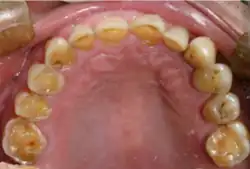

Frontal view of severe tooth erosion in GERD[26]

Severe tooth erosion in GERD[26]

Acid reflux into the mouth can cause breakdown of the enamel, especially on the inside surface of the teeth. A dry mouth, acid or burning sensation in the mouth, bad breath and redness of the palate may occur.[27] Less common symptoms of GERD include difficulty in swallowing, water brash, chronic cough, hoarse voice, nausea and vomiting.[26]

Signs of enamel erosion are the appearance of a smooth, silky-glazed, sometimes dull, enamel surface with the absence of perikymata, together with intact enamel along the gum margin.[28] It will be evident in people with restorations as tooth structure typically dissolves much faster than the restorative material, causing it to seem as if it "stands above" the surrounding tooth structure.[29]